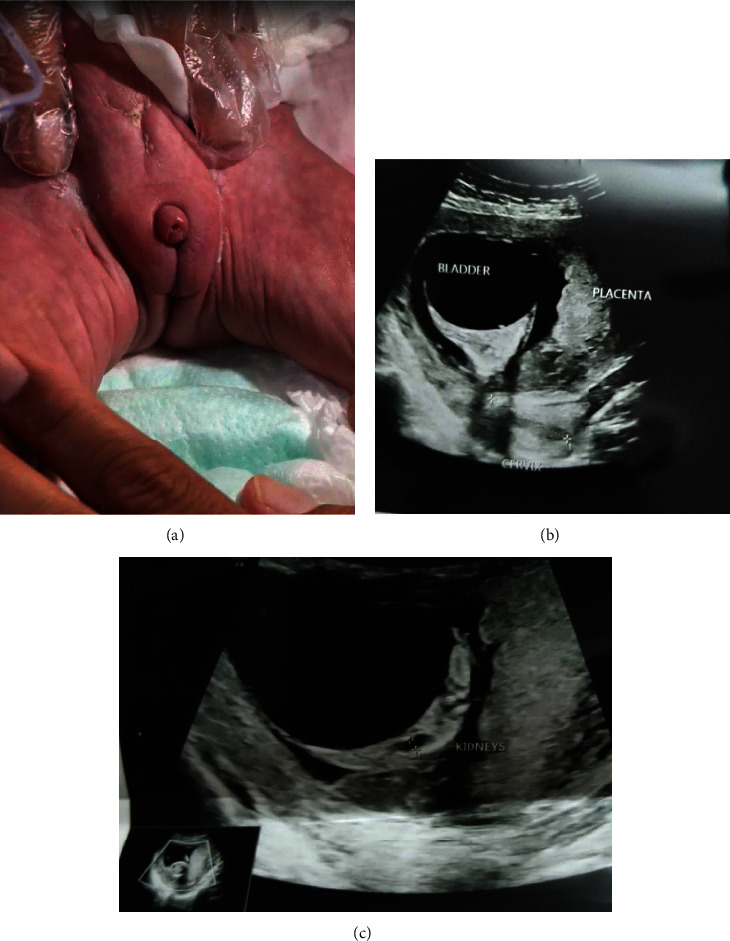

槑肚综合征(PBS)是一种罕见的先天性畸形,以腹部松弛、泌尿系统不同程度受累和隐睾三联症为特征。PBS 的确切病因尚不清楚。临床症状从死胎、明显的肾脏和呼吸系统异常到几乎正常的儿童都有。治疗通常包括手术修复腹壁缺损和泌尿道异常、早期睾丸切除术以及相关问题的支持性治疗。我们报告了首例体外受精诱导妊娠后患有 PBS 的女性新生儿病例,并对所有相关病例进行了全面系统的回顾。

Prune belly syndrome (PBS) is a rare congenital anomaly characterized by a triad of abdominal flaccidity, varying degrees of urinary system involvement, and cryptorchidism. The exact cause of PBS is unknown. Clinical symptoms can range from stillbirth to significant renal and respiratory abnormalities to almost normal children. Treatment typically involves surgical repair of the abdominal wall defect and urinary tract abnormalities, early orchiopexy, and supportive management of related problems. We report the first case of a female newborn with PBS following in vitro fertilization-induced pregnancy with a comprehensive systematic review of all relevant cases.